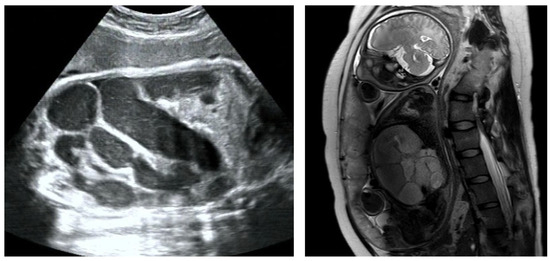

Based on the fetal ultrasound and MRI results, duodenal dilation was observed in 41 cases. In these cases, the dilated duodenum was connected to the gastric bubble, showing a typical sign like a double bubble (Figure 1). One hundred thirty-two ultrasound examinations were performed prenatally in these cases. GA at first time of diagnosis was 26.1 ± 4.5 weeks of gestation (range, 21+6–38+1 w). All these fetuses underwent an MRI examination prenatally and were confirmed with double-bubble sign. Subsequently, ultrasound was used to monitor the fetal development and changes in bowel dilatation. Each case received 3 ± 2 ultrasound examinations on average (1–9 examinations, mean = 3), with a continuous existence of double-bubble sign. Twenty-one cases were complicated with polyhydramnios. Forty newborns were confirmed to have congenital gastrointestinal malformations by surgical exploration in our department after birth, including twenty-one cases of annular pancreas (involving one case complicated with intestinal malrotation), sixteen cases of duodenal atresia (involving two cases complicated with intestinal malrotation), and three cases of atresia of the initial segment of the jejunum. Only one patient had no manifestations of intestinal obstruction after birth and was followed up for 1 year after discharge, with good growth and development. The accuracy of diagnosis of congenital duodenal obstruction using the fetal double-bubble sign was 97.6%.

Figure 1. “Double-bubble” sign in ultrasound and MRI examination.